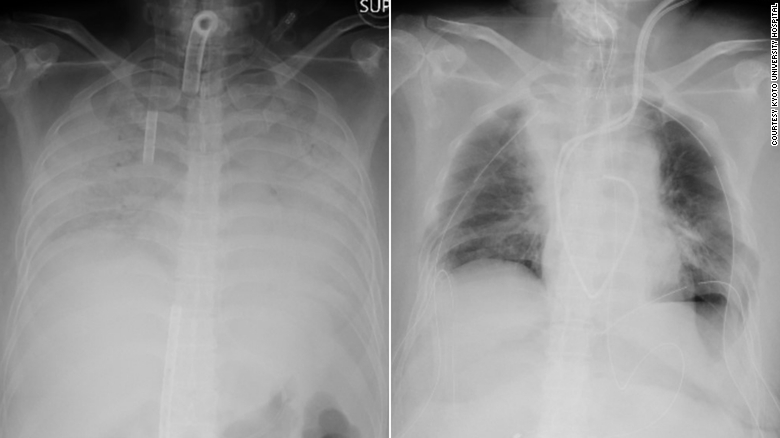

В среду, 7 апреля, группа из 30 медицинских специалистов Японии провела сложную операцию по пересадке легочной ткани. Операция длилась 11 часов. Донорами выступили супруг и сын пациентки. Операция проходила в медицинском учреждении, которое расположено в Киотском университете. По словам специалистов, это первый и единственный случай трансплантации легочной ткани от живых доноров.

Женщина из западной части Японии заразилась коронавирусной инфекцией COVID-19 в конце 2020 года. Несколько месяцев пациентка находилась на аппарате, который не давал ей умереть. По словам специалистов, недуг настолько сильно повредил легкие пациентки, что они не могли нормально функционировать.